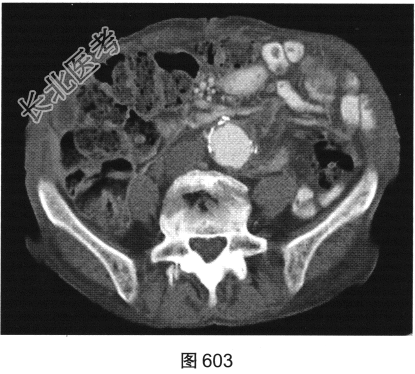

- [材料题] 患者女性,85岁,腹主动脉瘤破裂手术修复后,腹部疼痛。患者行腹部CT检查,见图603~图607。

- 简答题3、患者进一步行MRI检查,请对MRI影像特征描述一下。